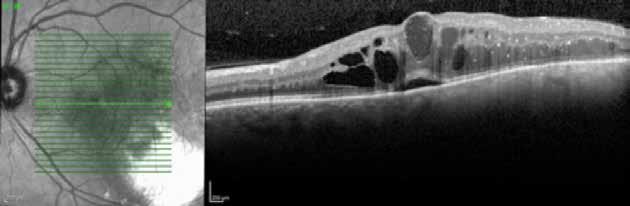

Type 3 MNV refers to the growth of vessels from the retinal circulation toward the outer retina. It is believed that vascular proliferation begins in the deep retinal capillary plexus, with the growth vector extending toward the outer retina. On FA and ICGA, Type 3 MNV appears as a hyperfluorescent intraretinal vascular complex with leakage in the late phases of the examination. Late-phase leakage ion ICGA is a unique feature of MNV lesions. Since these lesions originate from the retinal circulation, they never arise within the foveal avascular zone. Instead, they develop near its edge or at a variable distance from it, typically from the terminal portions of third-order arterioles and venules.5 (Figure 3)

Figure 3. Two examples of Type 3 macular neovascularization. In the first case, Indocyanine green angiography (B) and fluorescein angiography revealing the Type 3 macular neovascularization (arrowhead). Optical coherence tomography (C) showing the detachment of retinal pigment epithelium with the hyperreflective material related to the neovascularization. In the second case, optical coherence tomography (E) showing the intraretinal hyperreflective material related to the neovascularization with intraretinal fluid. Fundus autofluorescence (F) showing abnormalities of retinal pigment epithelium. Optical coherence tomography angiography (G) showing the neovascular lesion.